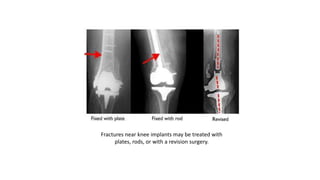

3. Fractures and knee replacements

These x-rays taken from the front (left)

and the side (right) show a fracture

near an artificial knee joint.

TREATMENT

• Those fractures are typically treated with rods or plates, just like

other distal femur fractures. In rare cases, the artificial implant must

be removed and replaced with a larger implant. This procedure is

called a revision and may be necessary if the implant is loose or not

supported by surrounding good bone.

Fractures near knee implants may be treated with

plates, rods, or with a revision surgery.